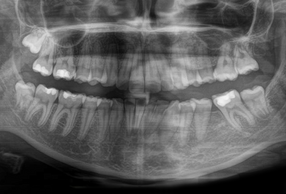

Ortopanoramica pre-trattamento della paziente. I due primi molari sinistri appaiono irrimediabilmente compromessi da carie destruenti

Ortopanoramica post-trattamento che mostra la chiusura degli spazi estrattivi